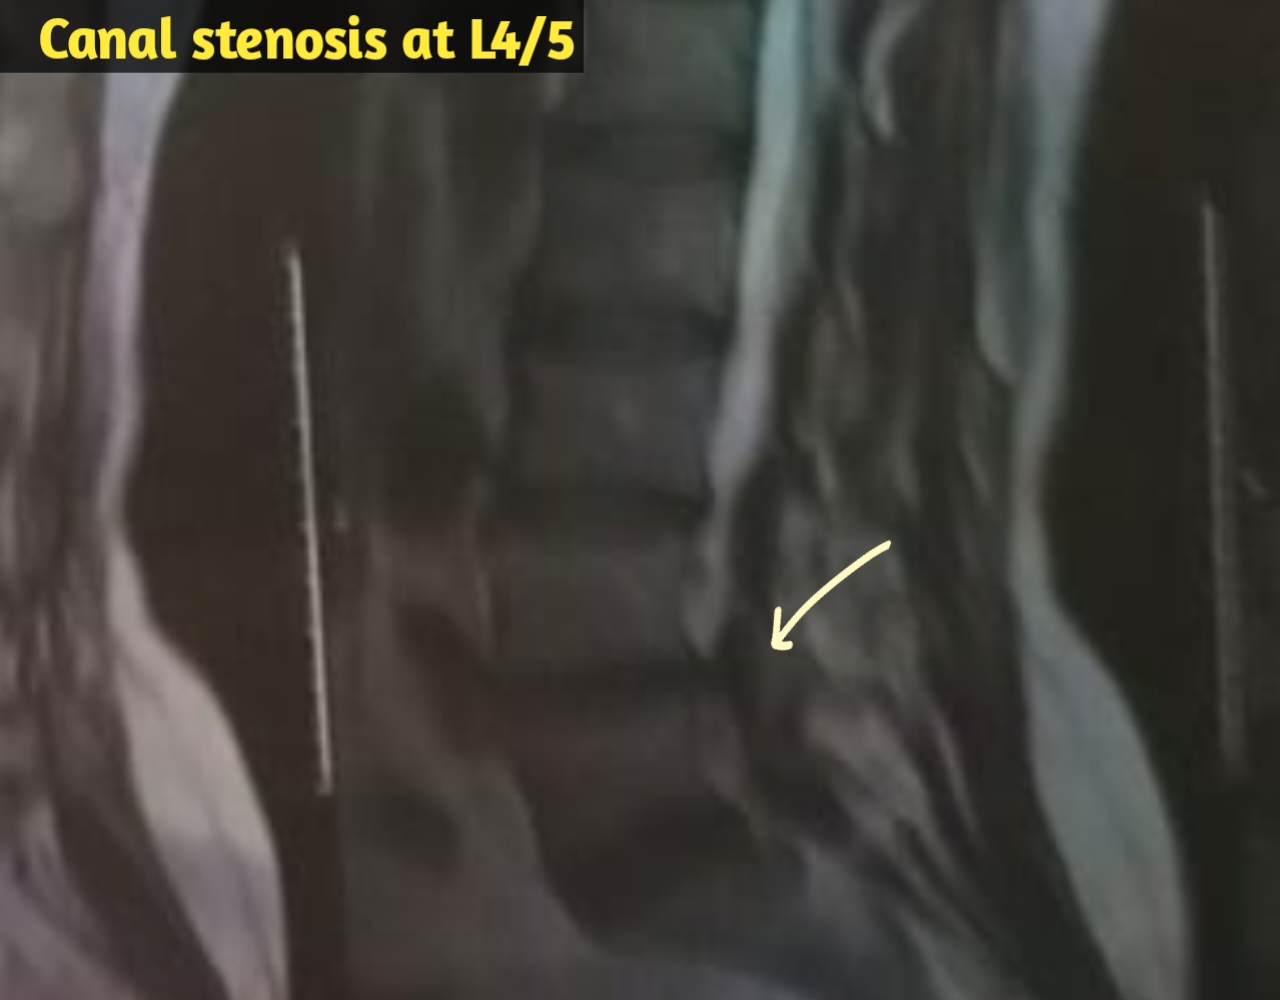

মাথা ব্যথা, ঘাড় ব্যথা, কোমর ব্যথা, পিএলআইডি সমস্যা, হেড ইনজুরি , স্পাইন ইনজুরি , স্পাইনের রড-স্ক্র ফিক্সেশন, মস্তিষ্ক - স্নায়ু - মেরুদণ্ড ব্যথা, স্পাইনাল টিউমার, ব্রেইন টিউমার, প্যারালাইসিস বা পক্ষাঘাত, স্ট্রোক, হাত - পায়ে ব্যথা, হাতে পায়ে ঝিমঝিম ভাব , শিশু নিউরোসার্জারি , ভাসকুলার নিউরোসার্জারি বিশেষজ্ঞ ও নিউরোসার্জন।